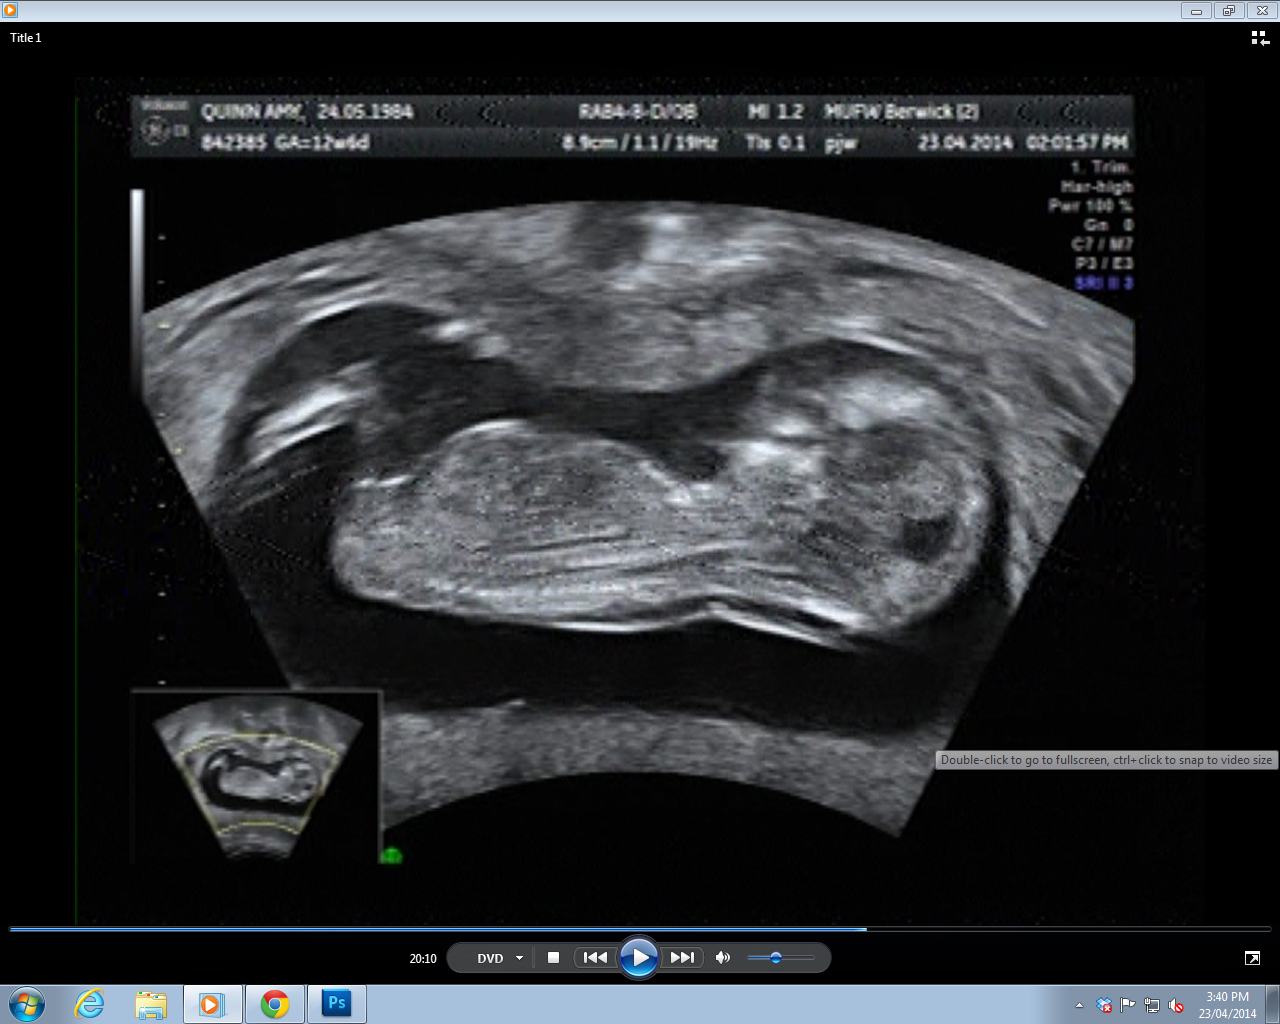

Three nub shots I was able to get, pulled off the DVD. I really didn't have much to work with - in 30 minutes of footage, these were the ONLY clear(ish) nub shots the whole time.

Attachment 18363Attachment 18364Attachment 18365